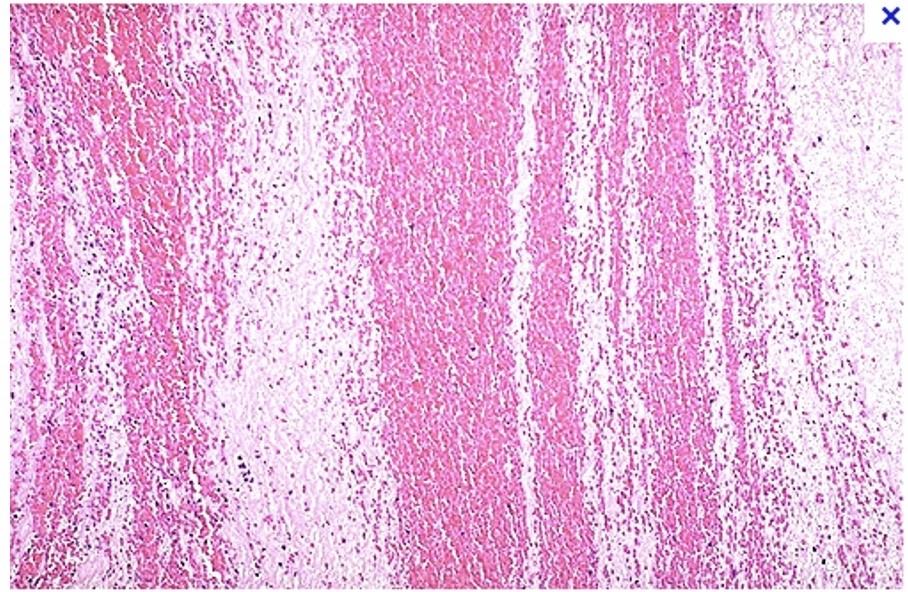

gross and microscopic alternating pale lines (platelets and fibrin) and dark line (red blood cells)

Lines of Zahn